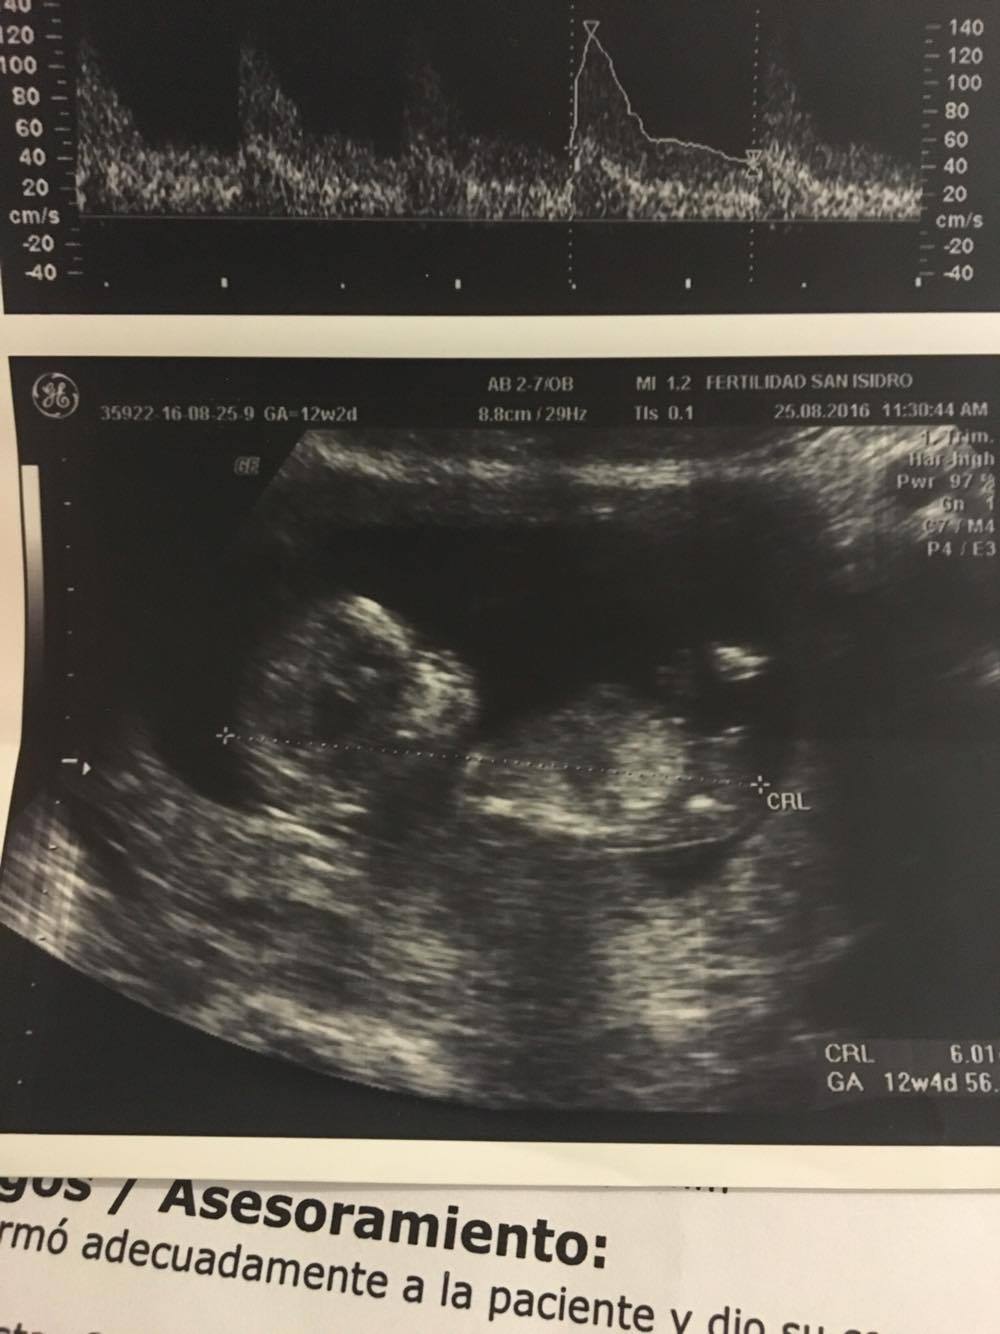

Hello, i'm really anxious to know what gender my baby is! can you help me? iŽll upload my 12 weeks ultrasound, SO.. IS IT A BOY OR A GIRL???

Attachment 32997

Leaning boy. Not sure the whole of the nub was captured though. Anymore pics?

mmm, this two help you?Attachment 32998